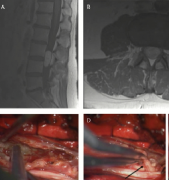

髓内脊髓肿瘤(IMSCTs),如下图所示,是指硬膜内 脊髓肿瘤 的一个亚群,由脊髓内的细胞产生,与相邻结构如神经根或脑膜相对。它们比脑瘤少见得多,据认为占中枢神经系统全部固有肿...

大多数脊髓髓内肿瘤患者起初可以通过尝试切除来治疗。不幸的是,那些不能行总切除或次全切除的患者,只能选择放疗和化疗...